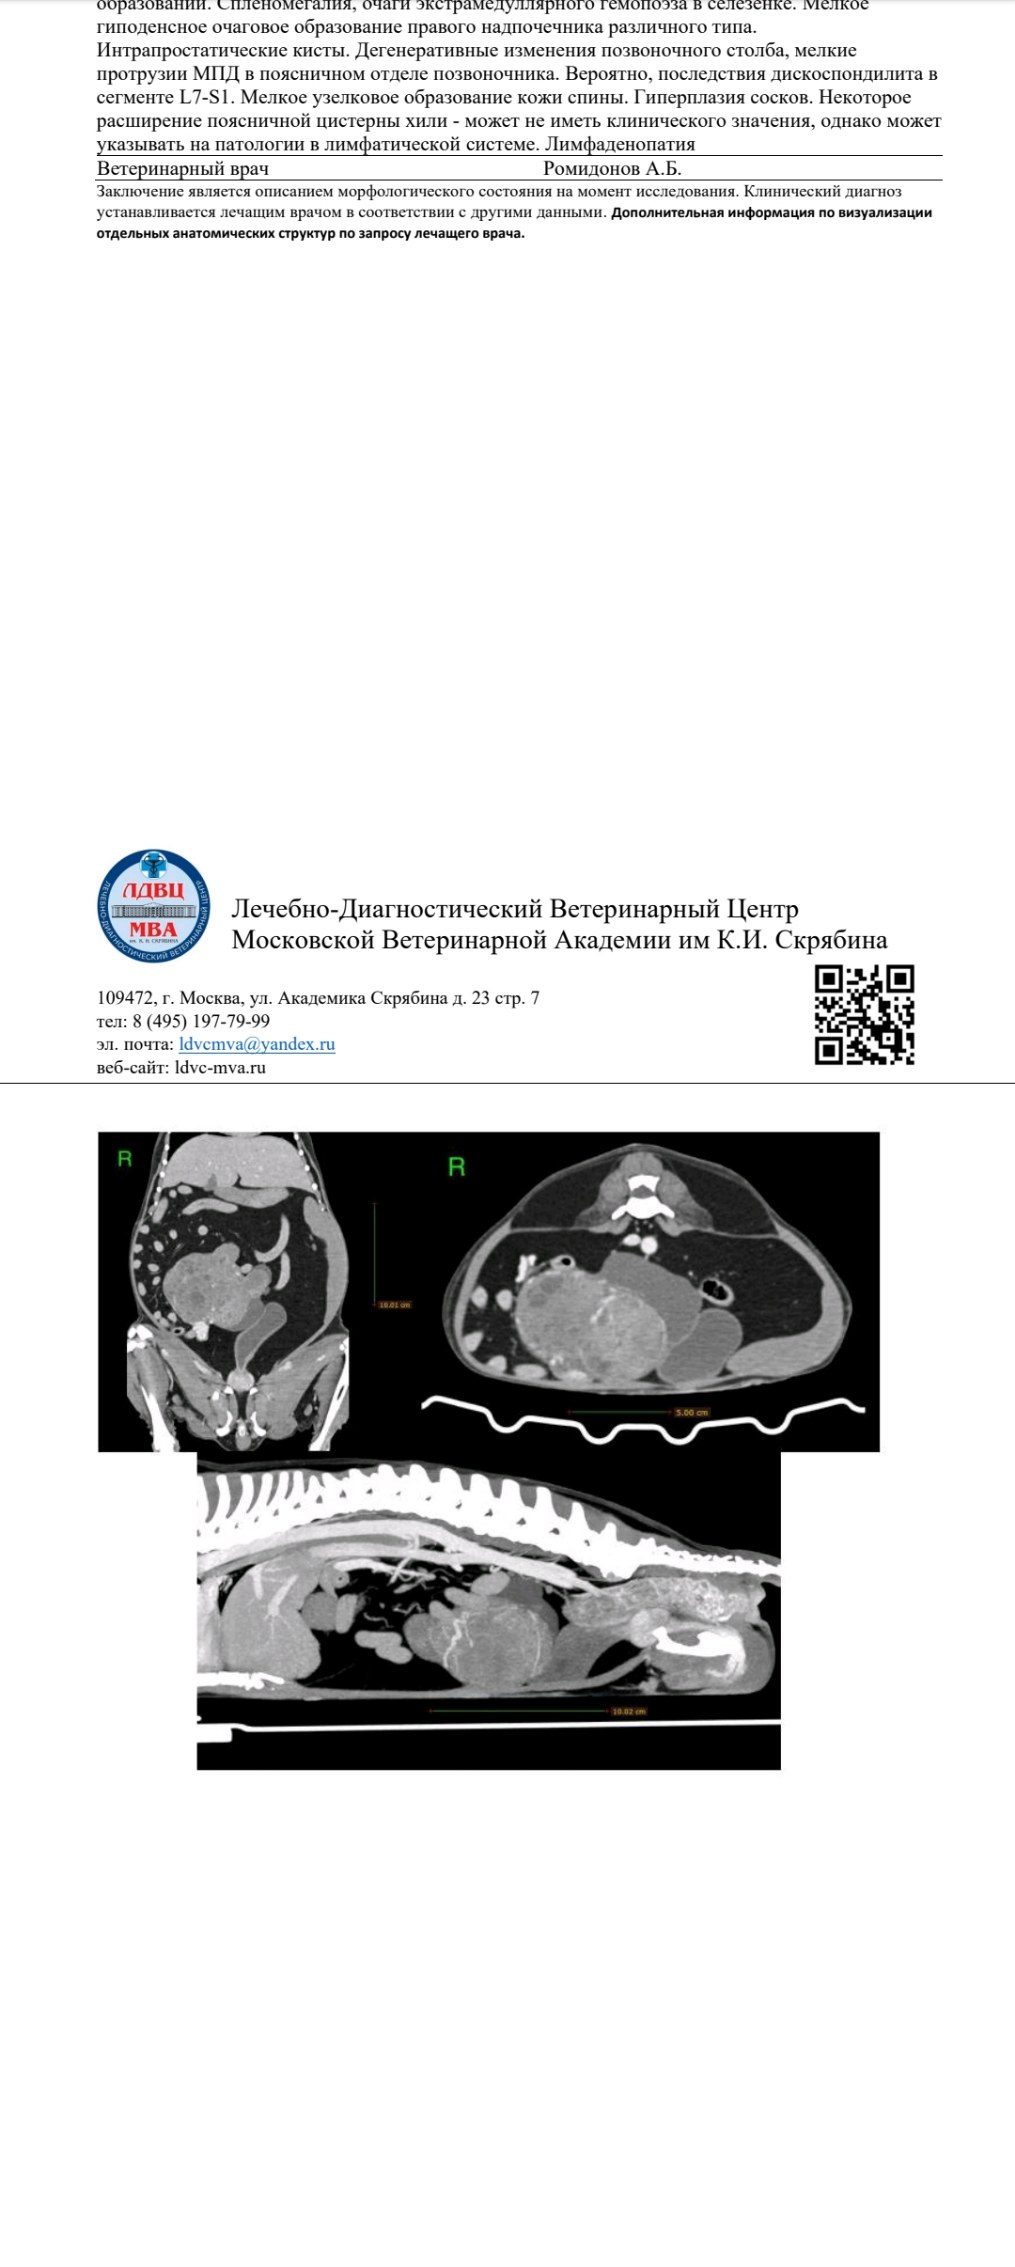

КТ брюшной полости

Вложения

Screenshot_2025-09-15-18-05-37-76_6431dcd7adc47d9b8b1ef172f656a796.jpg

Screenshot_2025-09-15-18-05-34-30_6431dcd7adc47d9b8b1ef172f656a796.jpg

Screenshot_2025-09-15-18-05-26-75_6431dcd7adc47d9b8b1ef172f656a796.jpg